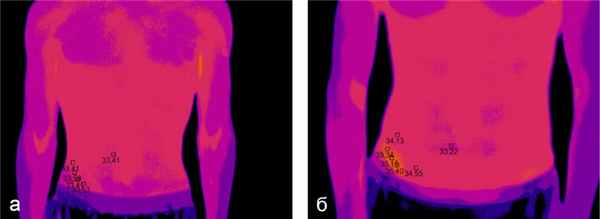

Для диагностики ряда поражений нервной системы, особенно с регионарными нарушениями кровотока, исследуют температуру кожи, которая меняется под влиянием ряда физиологических и особенно патологических процессов.

Сосудисто-вегетативные нарушения вследствие дисфункции механизмов большого и особенно промежуточного мозга, заболевания симпато-ганглионариого аппарата, реактивно-вегетативные ирритативные синдромы, заболевания периферической нервной системы сопровождаются изменением термотопографип кожи. Данные о «нормальной» температуре, по разным авторам, неоднозначны, что зависит от контингента обследованных и от применяемой методики термометрии.

Наибольшее диагностическое значение придается наличию термоасимметрии. Некоторые авторы относят к патологической разницу в 1°С. По нашим данным, о нарушении терморегуляции говорит разница температуры в симметричных участках кожи более чем на 0,5° С.

В настоящее время создан ряд инфракрасных радиометров для термометрии ограниченных участков кожи. Для получения видимых изображений термотопографии пользуются тепловизорами. Применяют так называемые сканирующие радиометры, в которых тепловые излучения преобразуются в электрические сигналы, а затем в видимые изображения на экране электроннолучевой трубки (термоскопия) или на специальной бумаге (термография). Современные тепловизоры могут регистрировать перепады температуры до сотых долей градуса.

Тепловизионные изображения представляют собой силуэты с непрерывным переходом от черного цвета к белому, в норме с симметричным расположением температурных полей. Применяют и количественную оценку термограмм путем сравнения их со шкалой полутонов или с помощью измеряющих приборов. Разрабатываются диагностические критерии термовидения и термографии при поражениях периферических сосудов, опорно-двигательного аппарата, хирургических, гинекологических и других заболеваниях.